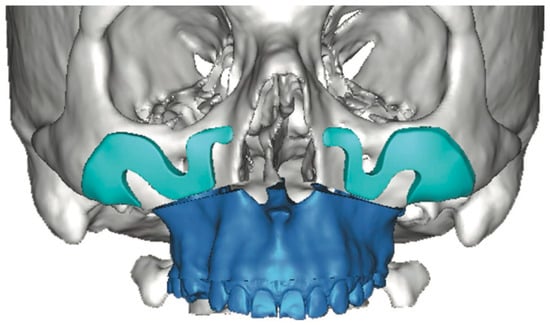

Reconstructing the Head and Neck region presents some of the most complex challenges in surgery, requiring not just technical precision but also creativity, collaboration, and innovation. In recent years, we’ve seen incredible progress thanks to advancements in areas like 3D printing, virtual surgical planning, augmented/mixed reality, artificial intelligence, tissue engineering, and biomaterials. Yet, while the tools at our disposal are more advanced than ever, the challenge remains: how do we translate innovation into better outcomes for our patients?

This Special Issue aims to bring together fresh insights, groundbreaking research, and real-world clinical experiences that are shaping the future of oral and cranio-maxillofacial reconstruction. We welcome contributions that explore novel surgical approaches, digital tools, regenerative techniques, and interdisciplinary strategies that improve both function and aesthetics for patients. Whether you're working at the bench or the bedside, we hope this collection will serve as a platform for sharing ideas that push the boundaries of what's possible in this evolving field.